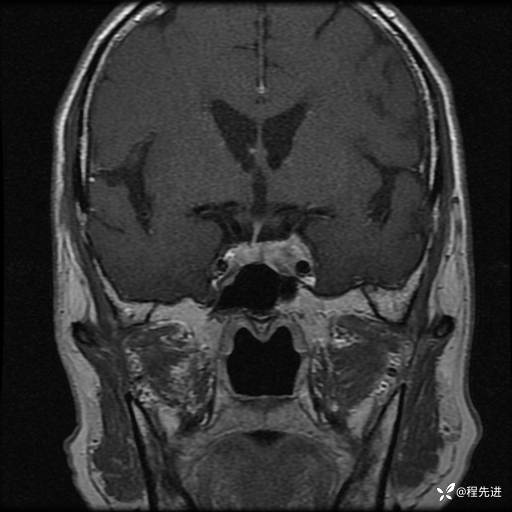

MRI平扫+增强:

T1:

T2:

T1增强: